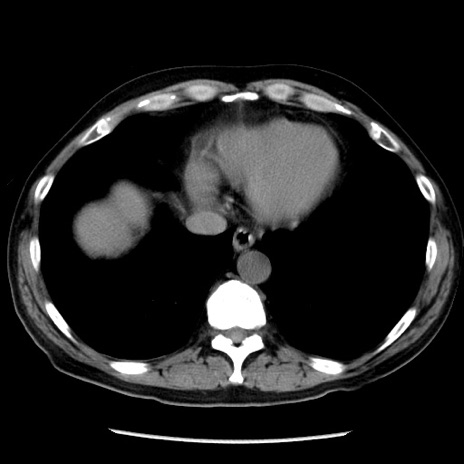

症例29(横断像)

【症例】40歳代男性

【現病歴】2日前から胃痛あり。徐々に周期的な激痛に変化した。本日になっても激痛があるため受診。

【身体所見】意識清明、BT 38-39℃台あり、腹部:膨満、やや硬、右下腹部に圧痛あり。

【データ】WBC 8500、CRP 23.26